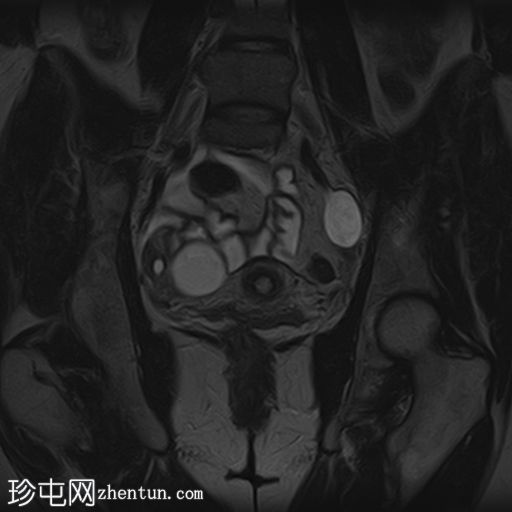

冠状位

T1

T2

已确诊3例卵巢囊肿:

右侧卵巢出血性囊肿,T1成像呈中等信号,T2成像呈高信号,伴有薄内部分隔

左侧卵巢出血性囊肿,信号特征与右侧囊肿相似

左侧单纯性卵巢旁囊肿,T1成像呈低信号,T2成像呈高信号

此外,所有囊肿均未显示弥散受限或实性成分强化。

所有囊肿均仅显示薄层外周壁强化。

道格拉斯囊右侧可见轻度积液。

卵巢相关囊性病变边界相对清晰。信号特征可能因出血时间而异。

T1 加权成像:大多数病变呈低信号,也可能包含中至高信号成分。

T1 脂肪饱和度:通常显示中至高信号。

T2 加权成像通常显示高信号。 T2 阴影征提示存在慢性血液产物,更像子宫内膜异位症。

T1 增强钆:未见强化。

本例卵巢囊肿呈中等 T1 信号,类似于肌肉信号,T2 信号高,伴有薄内隔和外周壁强化。但无内部强化或弥散受限。STIR 序列显示与 T2 一致的信号,无任何脂肪成分。该表现提示卵巢出血性囊肿处于早期或消退期。

此外,左侧卵巢旁囊肿外观简单,T1 信号低,T2 信号高。